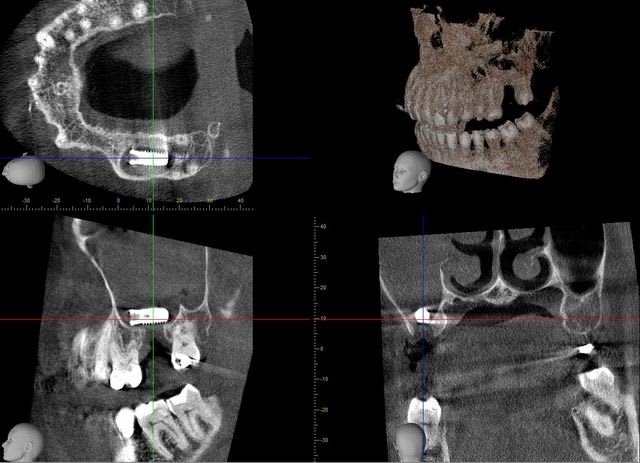

autres coupes...

3f3boxni50k58rq7e9ce9ddqrxgk - Eugenol